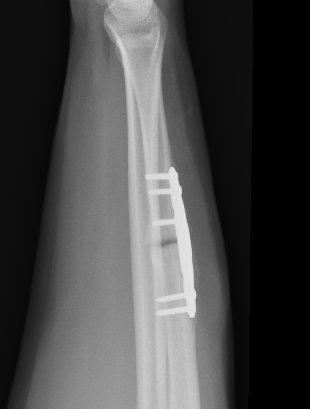

Operative management

Indications

Acute fractures

- > 50% displacement

- > 10 degrees angulation

- midshaft ulna fractures - higher risk of nonunion

Options

Compression plating

Technique